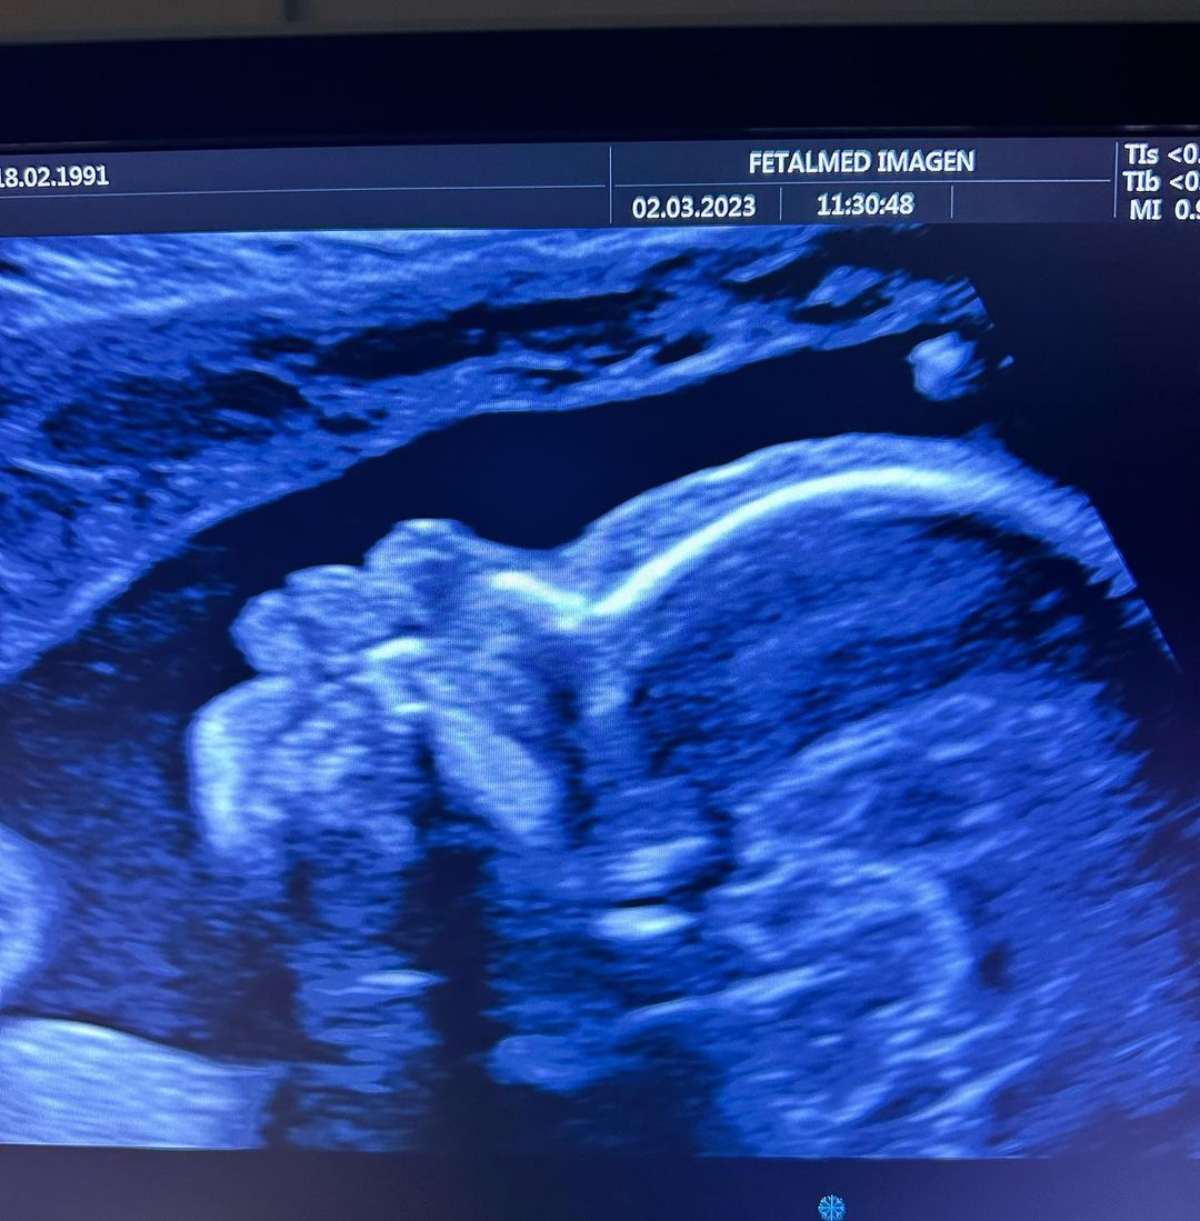

En esa línea, recientemente Vale Roth mostró una nueva ecografía, en la que ya se puede apreciar el rostro de su bebé y una de sus manitas.

"Así que acá me pueden ver en mi semana 25, estoy pesando 740 gramos y mido 33 cm. Estoy muy grande y seguiré creciendo", añadió.